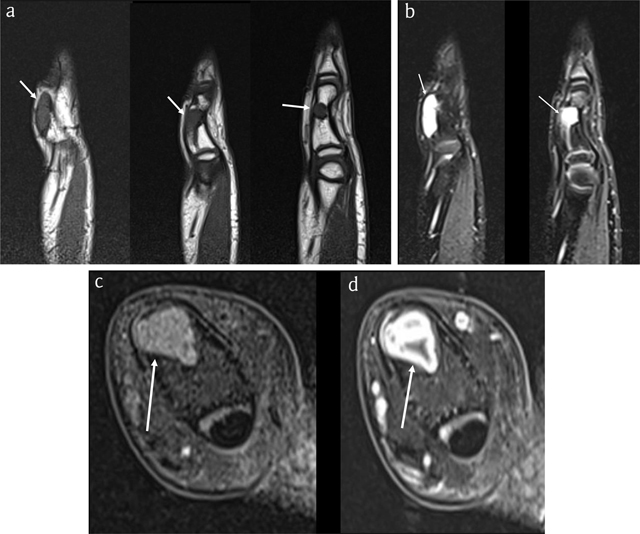

Figure 2

Case 1 – MRI. Sagittal T1-WI (3 adjacent slices) (a). Sagittal fat-suppressed (FS) T2-WI (2 adjacent slices) (b). Axial FS T1-WI (c). Axial FS T1-WI after intravenous administration of gadolinium contrast (d). The lesion is isointense to muscle on T1-WI (arrows in a) and hyperintense on FS T2-WI (arrows in b) and enhances peripherally, in keeping with chondroid matrix (arrow in d).